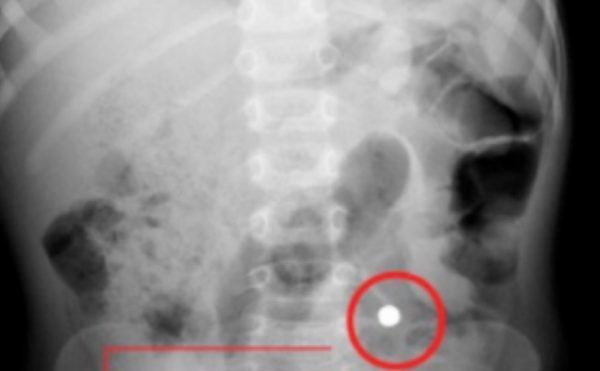

Dopo numerosi ed accurati accertamenti però si è scoperto che quello che sembrava un tumore polmonare era un corpo estraneo facilmente estraibile. I medici hanno così disposto l’intervento per l’espulsione e quando hanno estratto il corpo estraneo con grande stupore hanno notato che si trattava di un nocciolo di ciliegia. Una vicenda che ha dell’incredibile, ma che fortunatamente ha avuto un lieto fine per l’uomo.